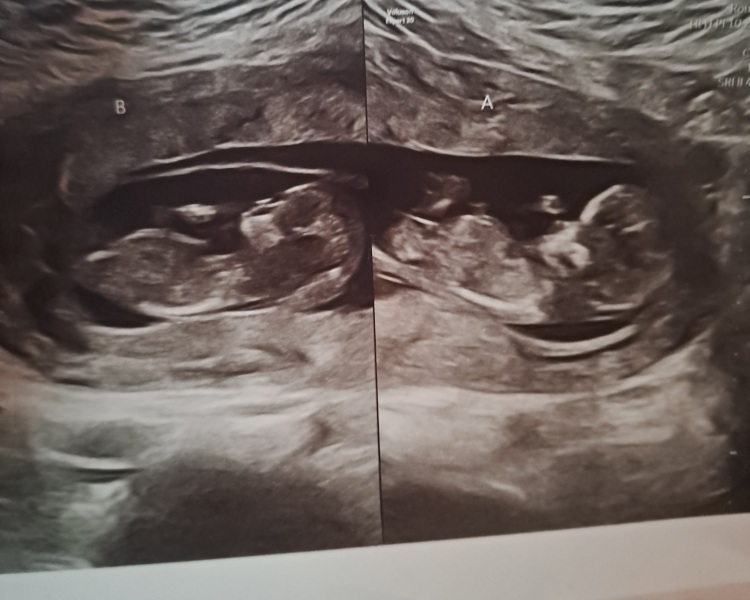

Hi all. I have found out I am expecting DCDA twins in January. I have 2 other children and loved giving birth. I had two water births and I don't think I would have survived without being in the water.

Almost 7 months in, and all my worries vanished the moment they were born.

A wonderful, quick, vaginal delivery with no intervention. B was born breech. Girls came at 35+1 on Christmas Eve, and we were home on boxing day. Still breastfeeding with the occasional bottle of formula.